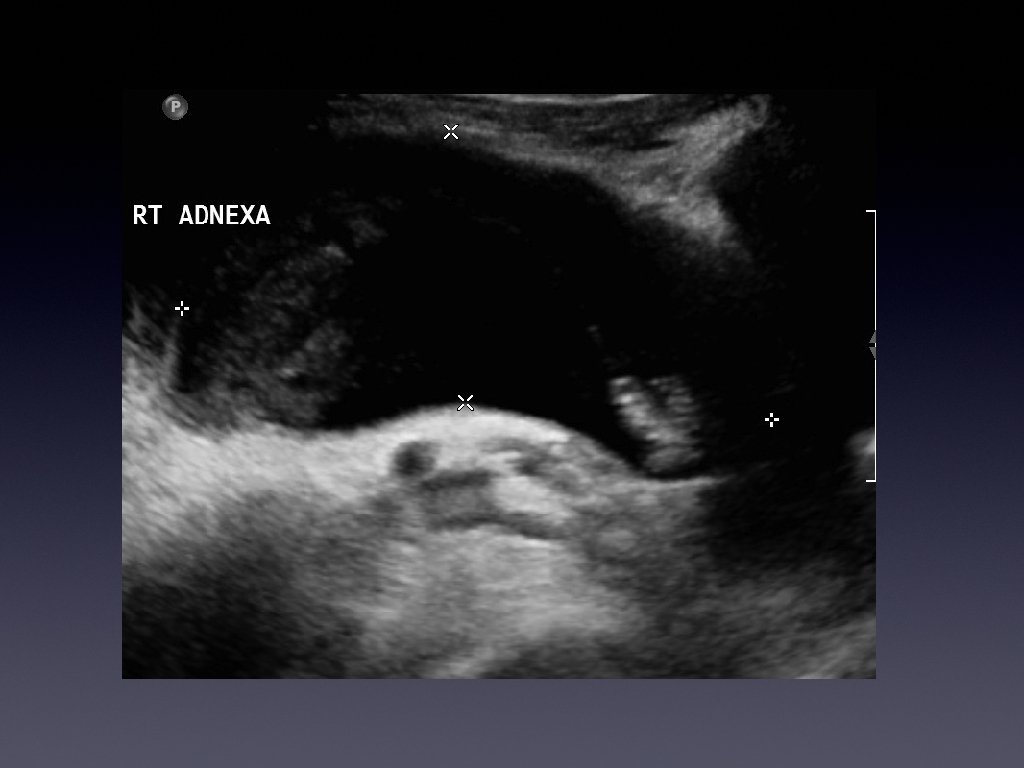

Presentation • • • 36 year old female Presented with chronic right iliac fossa

Presentation • • • 36 year old female Presented with chronic right iliac fossa pain Tenderness on palpation Bloods normal Investigated further with a pelvic ultrasound

Learning Points • • • Hydrosalpinx is usually a tubular cystic mass However it

Learning Points • • • Hydrosalpinx is usually a tubular cystic mass However it has septations Septations are caused by the normal fold present in the fallopian tube which become thickened with inflammation.

Learning points • • • Usually a cystic mass Variable internal echogenicity Devoid of

Learning points • • • Usually a cystic mass Variable internal echogenicity Devoid of septations Can have debris Not every tubular mass in the iliac fossa is ovarian in origin!!!!